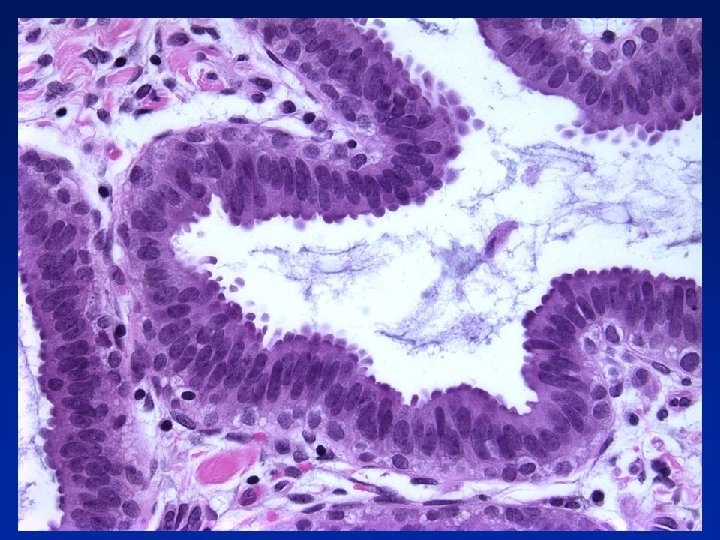

Columnar Cell Change • Columnar epithelial cells (1 or 2 cell depth) line • • • TDLU, often mildly dilated Uniform, ovoid nuclei Perpendicular to basement membrane Cytologically bland Mitotic figures rare Apical snouts often present Secretions may be present in lumen with Ca 2+

Columnar Cell Hyperplasia • Similar to CCC, but stratification > 2 cells depth • Nuclei morphology as in CCC • May be more crowding & overlapping of nuclei • Tufts or hummocks mimicking micropapillae • Exaggerated apical snouts - hobnail appearance • Intraluminal secretions often with Ca 2+ N. B. If true micropapillae, bridges, cribriform pattern etc = consider as ADH/DCIS

Flat Epithelial Atypia • TDLUs often darker than normal at low power • 1 or more layers of monotonous, cuboidal to • • • columnar cells, resembling LG DCIS Round nuclei Mild increase in nuclear/cytoplasmic ratio Dispersed or marginated chromatin Nucleoli sometimes more prominent Mitotic figures rare May be scattered lymphoid cells

Not necessarily flat